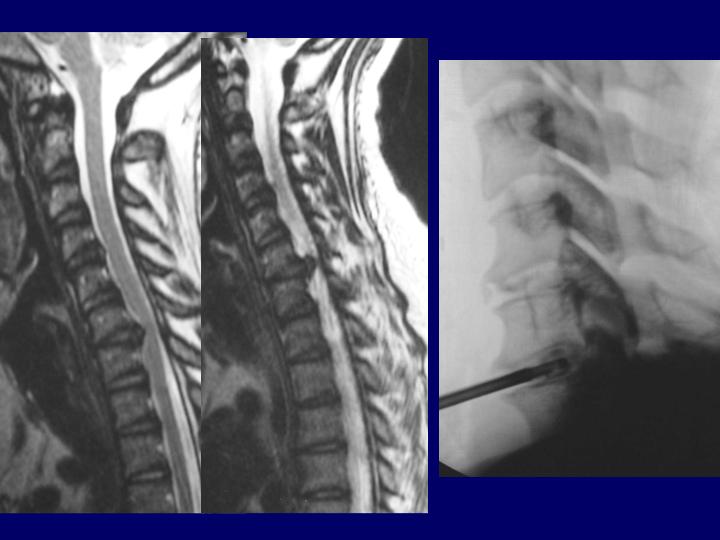

Hernias Discales